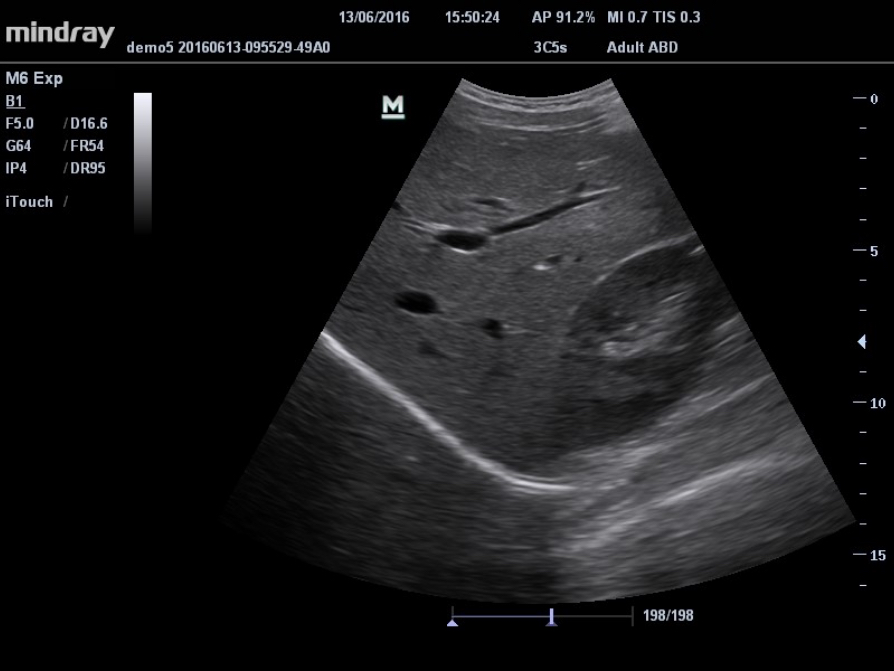

??

?? ? ??

??? ??? ?? ?? ?? 8?? ?? ??, ??? ?? ???? ?? ?? ??? ?????.

iClear? (??? ?? ??)

?? ?? ?? ???? ??? ?? ?? ??.

? ?? ???? ???? ?? ??

? ???? ??? ??

? ?? ??? ŌĆś??? ??ŌĆÖ

iBeam?(?? ?? ??)

?? ?? ?? ??? ???? ?? ??? ??? ? ?? ?? ???? ???? ???? ???? ? ????.